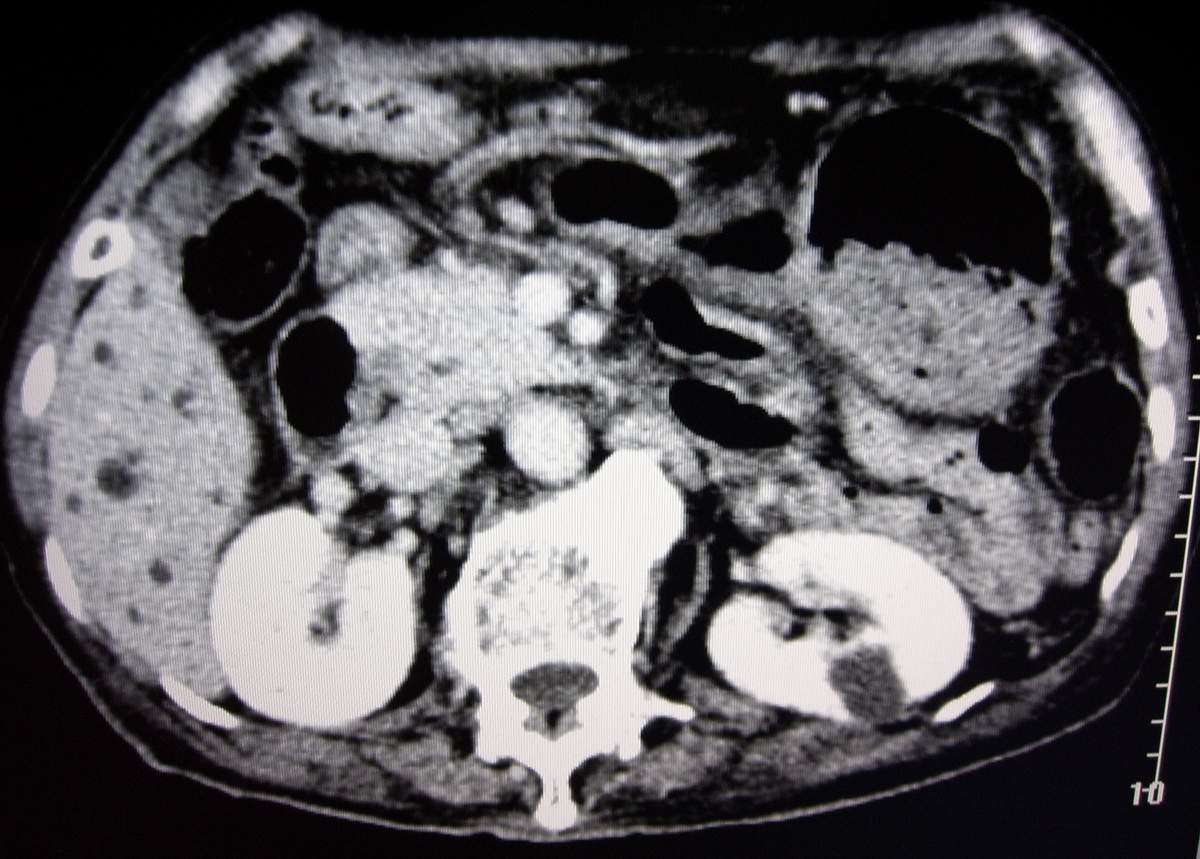

男,77岁,病史不详。

肝内胆管扩张、主胰管扩张 ,胰头影大,考虑胰头癌或胆管下端癌侵犯胰腺可能性大

另外见:胆囊结石 左肾囊肿

肝内外胆管明显扩张,但是程度较轻,应该是个慢性的过程,增强扫描后未见明显异常强化,胰管增宽、扩张考虑为胰头部占位性病变。

慢性胆囊炎,胆结石,左肾囊肿肝内胆管扩张,胰头大,考虑胰头癌

慢性胆囊炎,胆结石,左肾囊肿,胰头癌伴肝内胆管、胰管扩张,不除外侵犯肠系膜上静脉的可能。

肝内外胆管明显扩张,肝门区见软组织密度肿块,胆囊壁增厚,胆囊扩大。胰头不大。考虑:肝门区胆管细胞癌。

肝内胆管扩张明显,cbd未见明显扩张,胰管轻度扩张,肝门部胆总管癌?

肝内胆管普遍扩张,呈串珠状改变,走行不规则,且右叶胆管周围肝实质密度呈条片状减低,未见占位性病变,外周胆管及胰管扩张不及肝内胆管.胰腺钩突形态正常,胰十二指肠区域未见明显结节及肿块,初步考虑慢性胆管炎可能性大.请结合临床病史.另外用宽窗看一下吉氏筋膜有无增厚.

1肝门区域软组织影,肝内胆管明显扩张,胰管轻度扩张。考虑肝门区胆管细胞癌。2胆囊结石。3左肾小囊肿。

1 肝内外胆管扩张,肝内明显,胰管扩张,胰头明显增大,符合胰头癌双管征。2 胆囊壁略增厚,胆囊内可见高密度结石影,胆囊炎、胆结石3 左肾囊肿